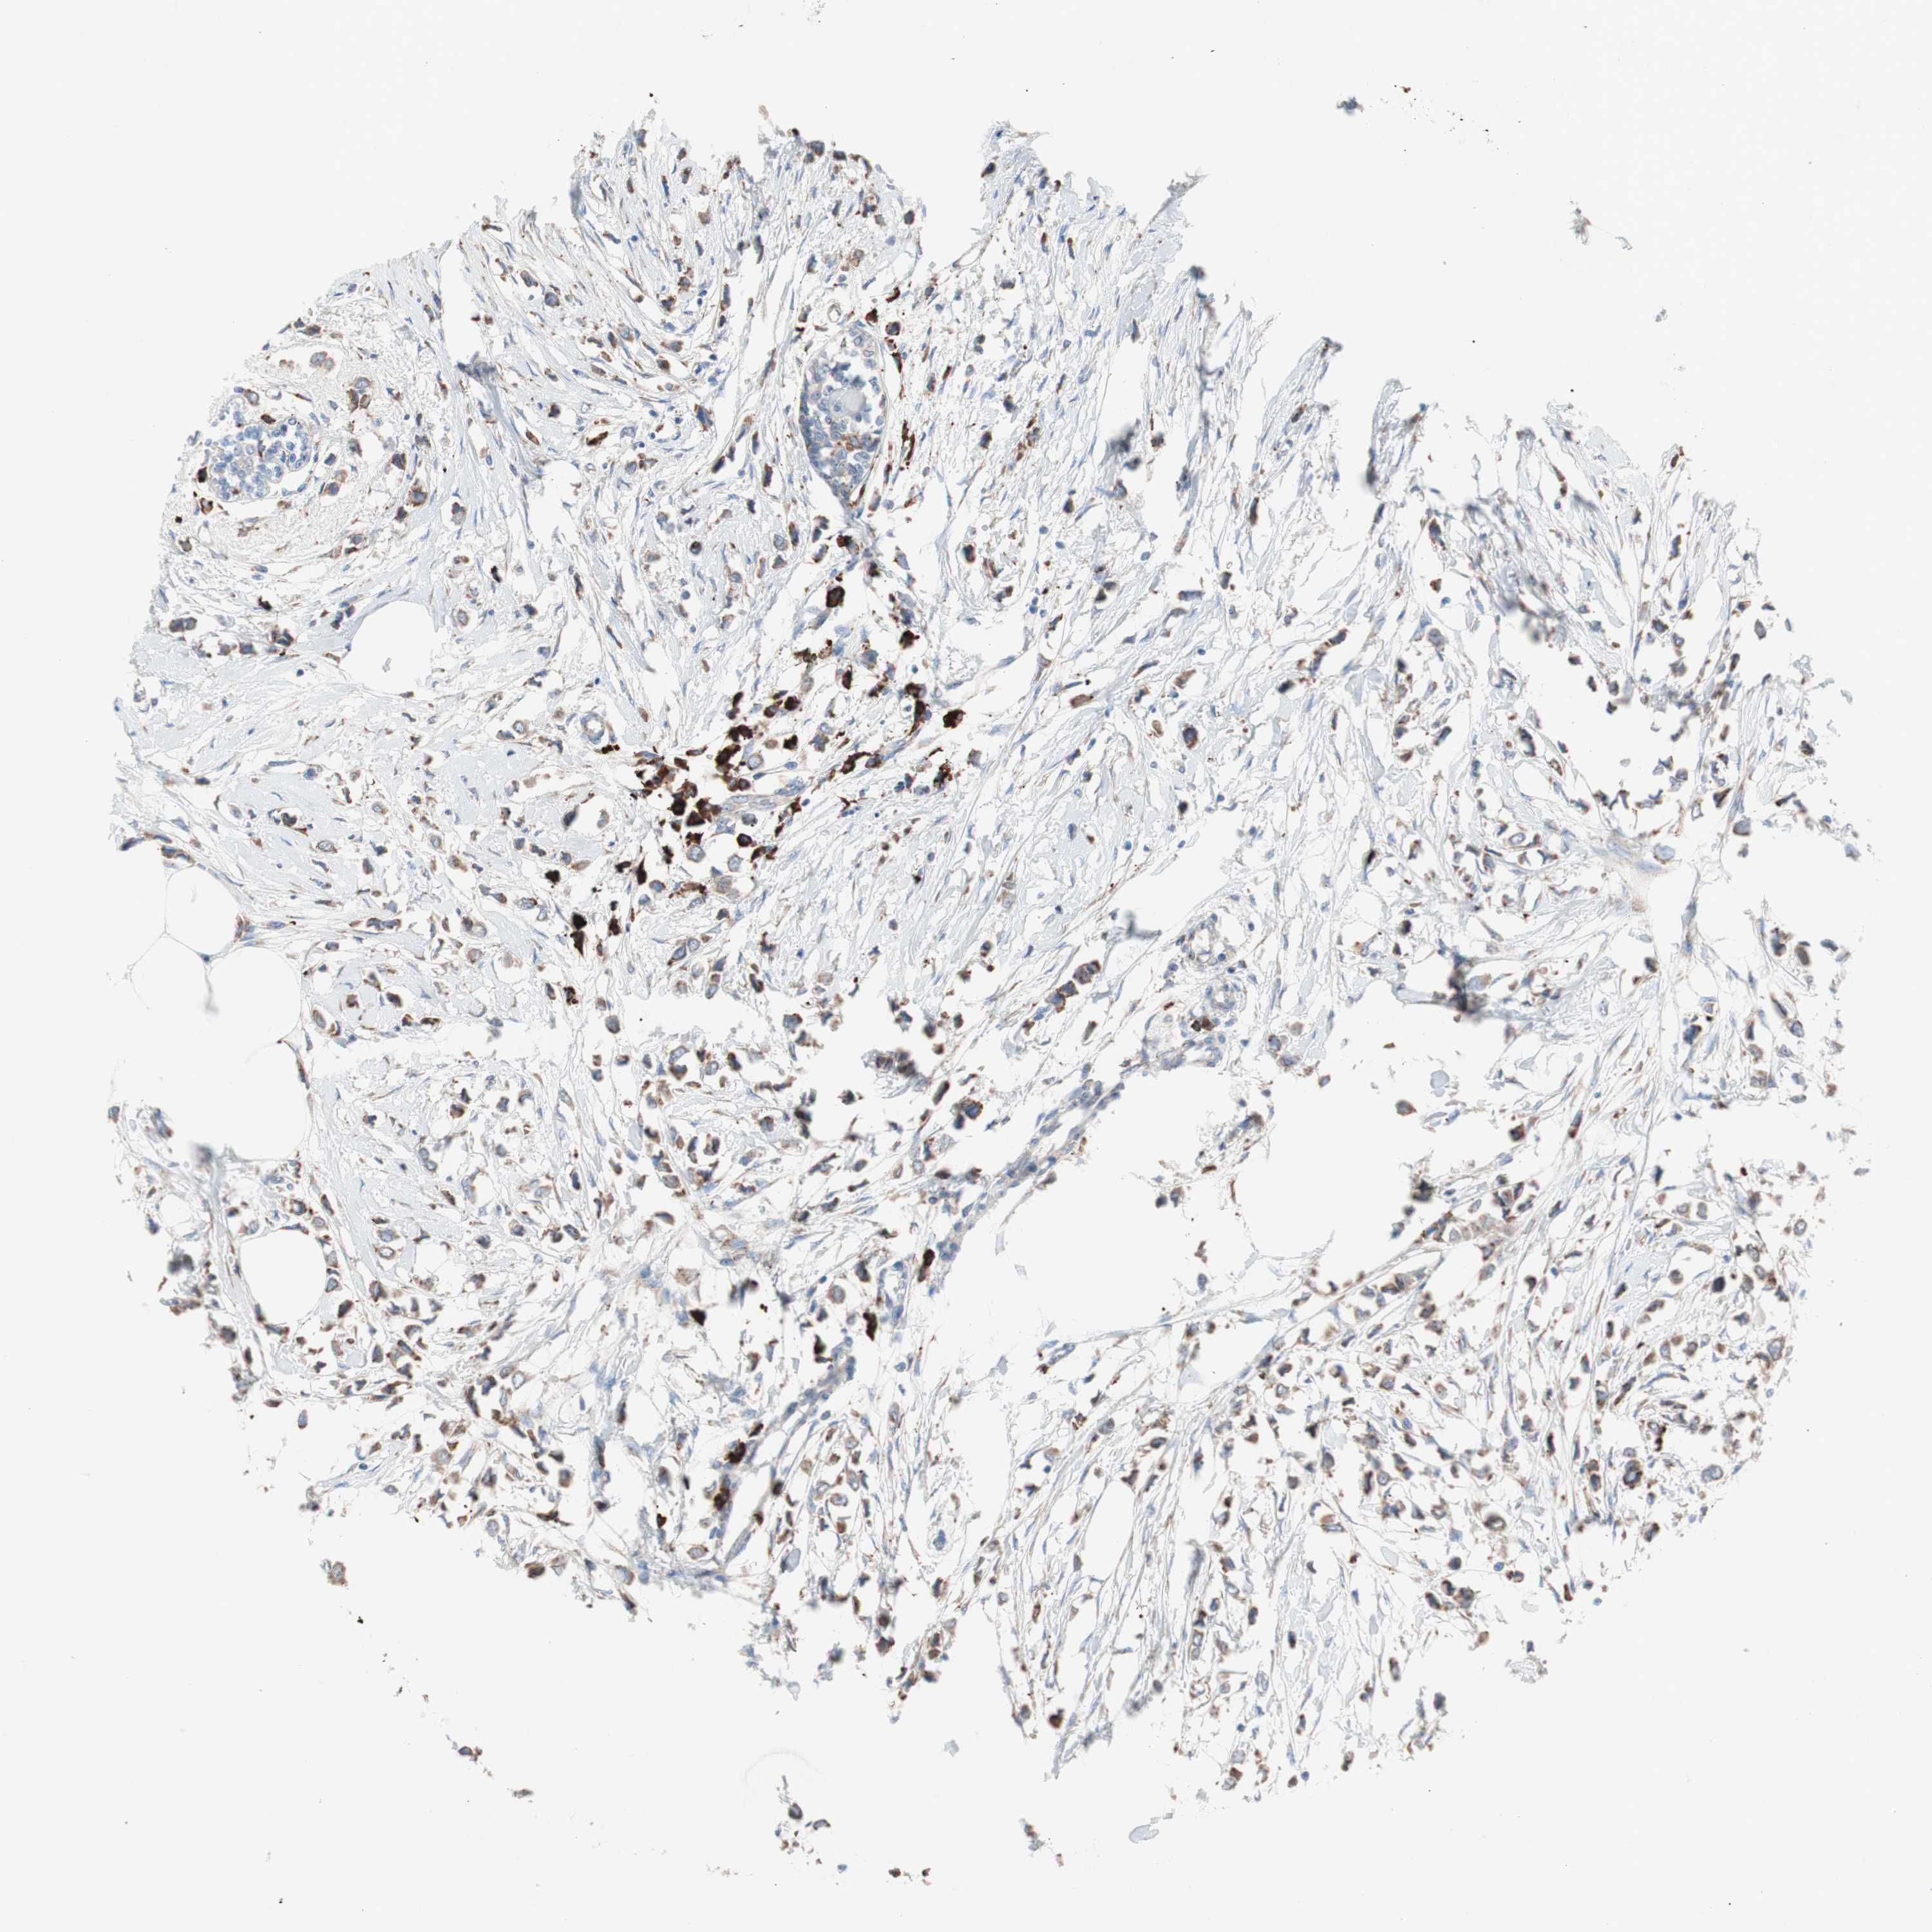

CANCER BREAST CANCER Show tissue menu

BRCA TCGA BRCA VALIDATION PROTEIN EXPRESSION